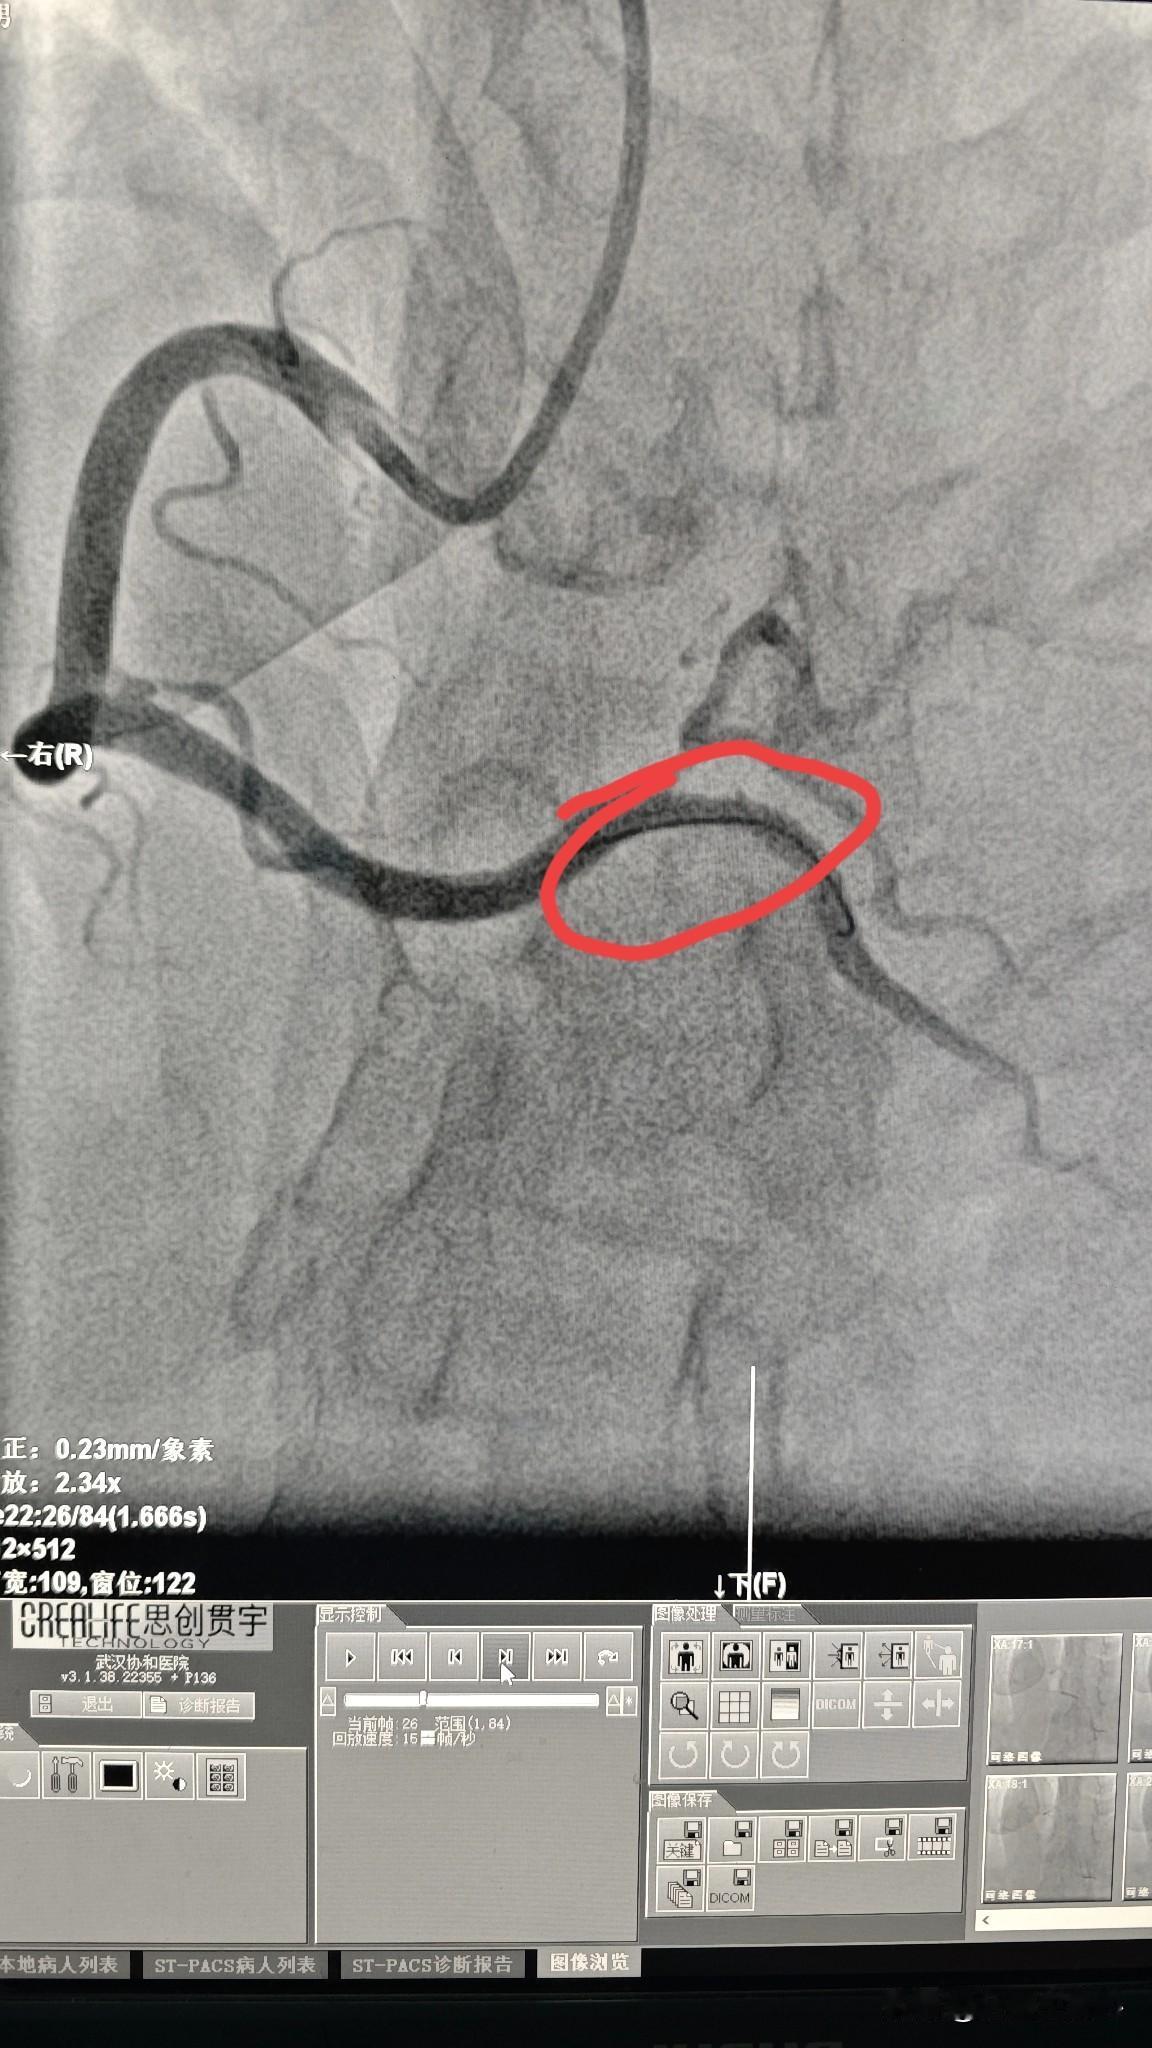

38 岁男性冠状动脉三支病变!38 岁男性患者,有高血压、糖尿病,近期还突发脑梗,老年病都全乎了。经过一段时间治疗,病情逐渐平稳。因心电图显示心肌缺血,考虑到全身多个器官的血管都有动脉硬化,就做了冠脉造影检查,结果显示三支病变(前降支、回旋支、右冠状动脉)。 在急性脑梗期间做冠脉支架风险较高,药物治疗了6个月后,先做了右冠状动脉,造影显示粗大的右冠状动脉远端有重度狭窄,做了一个支架后,血流恢复通畅。 前降支和回旋支的狭窄留作后续治疗,让患者先休养一段时间再说。年轻并不是不会得心脑血管疾病,而是需要更加注意平常生活。 如果有心脑血管疾病的家族史,在年轻时候就要注意体检查血糖、血脂、血压和动脉硬化的情况,饮食方面也要注意低盐低脂饮食,不吸烟,控制好这些危险因素,就能少患上这些慢性病。 如果已经出现了血压、血糖、血脂问题,尽早发现尽早干预和治疗,避免发展到冠心病阶段。